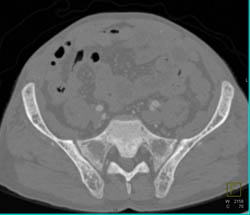

GSW to Femur With Soft Tissue and Muscle Injury